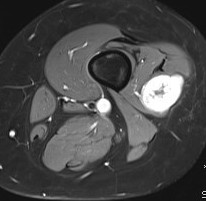

Show lesion on nerve periphery compared with neurofibroma which is in center of nerve

Schwannoma on tibialis posterior nervee

Schwannoma on tibialis posterior nerve